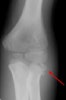

X-ray : 요골두 골절(Radial head fracture)

보통 AP, lateral, both oblique 즉 4장의 사진을 모두 찍어야 미세한 골절을 찾아내기 수월합니다.

필요시 요골두-소두 촬영을 실시합니다.

잘 보이지 않는 유리체나 골편, 동반된 골절 등의 확인에 CT가 도움을 줍니다.